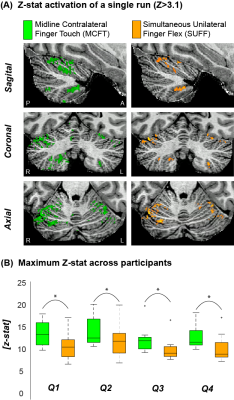

Both tasks resulted in significant activation for all participants in all four quadrants. MCFT resulted in significantly higher maximum Z-stats than SUFF across participants (P<0.05, paired t-test, Fig-2).

Figure 2: Example activation maps and maximum Z scores (A) The z-stat activation (Z>3.1) of a single run for MCFT and SUFF presented in three orientations (Sagittal, Coronal and Axial) (B) The maximum z-score for each task across participants. Note that the MCFT task resulted in significantly (paired t-test P<0.05) higher max z-stats compared to the SUFF task in all quadrants. Q1=upper right quadrant Q2=Upper left quadrant Q3=Bottom right quadrant Q4=Bottom left quadrant